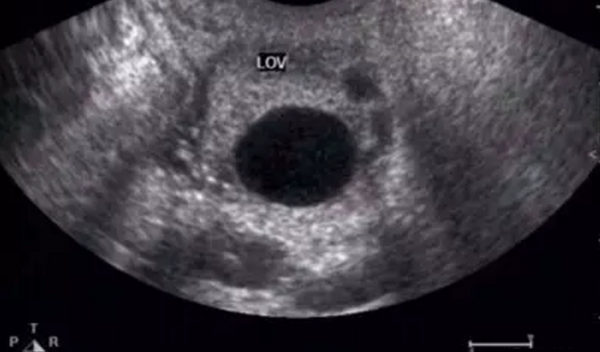

正常成熟的优势卵泡的声像图

①卵泡最大直径达20mm,优势卵泡最大直径范围为17~24mm,体积2.5~8.5mm⊃3;。径小于17mm者为非成熟卵泡。

优势卵泡的声像图

②卵泡外形饱满呈圆形或椭圆形,内壁薄而清晰,或可见内壁卵丘所形成的一金字塔形的高回声,多在排卵前24~30小时易于显示。亦可见优势卵泡周围有一低回声晕(多由排卵前卵泡膜组织水肿所致)。

③卵泡位置移向卵巢表面,且一侧无卵巢组织覆盖,并向外突出。

自然周期中优势卵泡的生长速度大约为(1~2)mm/d,近排卵前的卵泡最大生长速度可达(2~3)mm/d,卵泡直径达18~28mm时成为成熟卵泡。